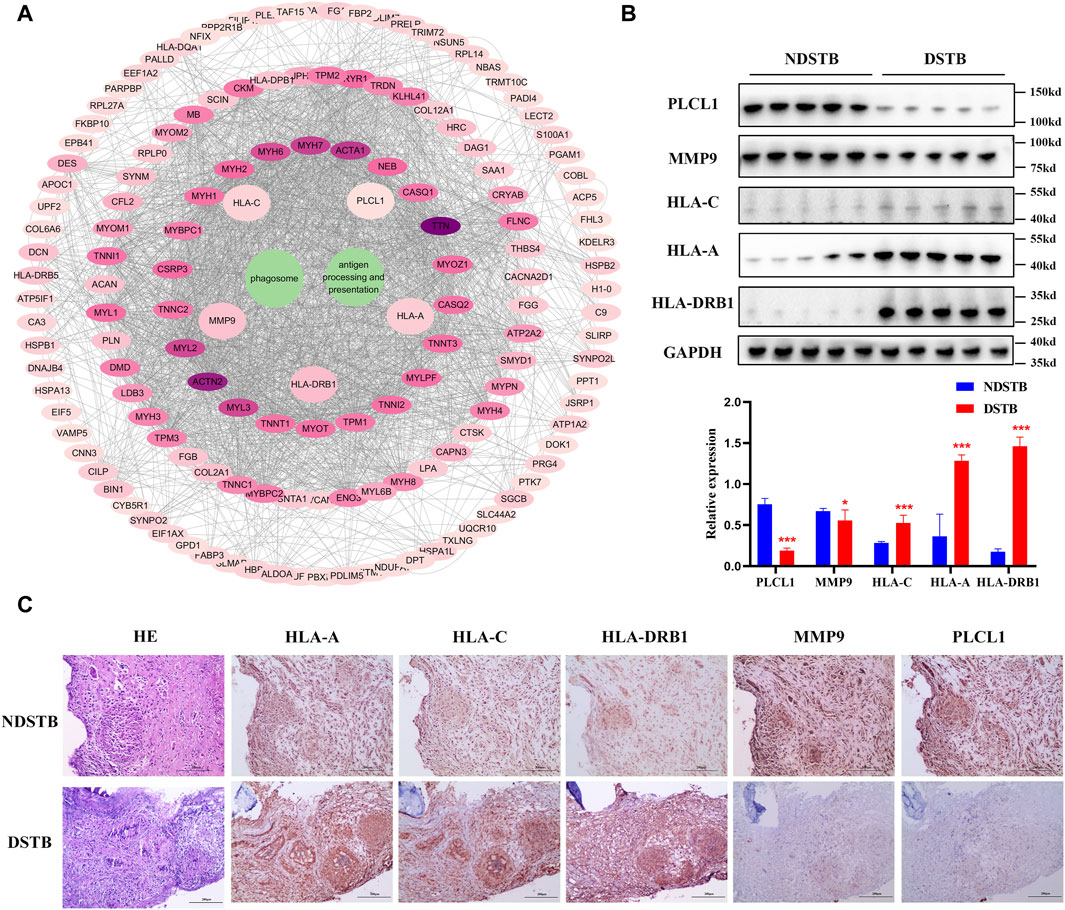

PPI analysis confirmed by Immunohistochemistry and Western blot analysisThrough KEGG signaling pathways analysis, it was revealed that HLA-DRB1, HLA-A, HLA-C, MMP9, and PLCL1 among the 25 DEPs were linked to “Antigen processing and presentation” and “Phagosome” pathways (as depicted in Figure 6A). To further exprole, results revealed that the expression of MMP9 and PLCL1 were remarkably decreased in the focal tissues of DSTB, compared with NDSTB. Contrarily, the HLA-A, HLA-C, and HLA-DRB1 were significantly increased in the focal tissues of DSTB, compared with NDSTB (Figures 6B,C), suggesting that five proteins (HLA-DRB1, HLA-A, HLA-C, MMP9 and PLCL1) may be involved in Rifampicin-resistant STB.

Figure 6. (A) “DEPs-drug-resistant spinal TB- “Antigen processing and presentation “pathway -“Phagosome” pathway -DEPs-Targets” network. Protein-protein interaction network using STRING. A PPI of all detected DEPs. The significantly enriched pathways (p < 0.05) and protein/protein coding gene and protein-protein interaction network associated with the pathways. The innermost circle is 5 of the key proteins of DEPs. The darker the color, the greater the degree value. The criteria for sub-setting was the more and denser the edges, the more central the protein was. The innermost five key proteins in the circle are most relevant to these two pathways. These proteins are particularly relevant to the mentioned pathways, with green highlighting their involvement in “Antigen processing and presentation” and “Phagosome.” (B) Relative expression of MMP9, PLCL1, HLA-A, HLA-C and HLA-DRB1 measured using the tissue protein of DSTB and NDSTB were tested by Western blot (n = 5). Statistically significant differences between groups were determined using a Student’s t-test or two-tailed one-way analysis of variance, followed by a Student-Newman-Keuls test; *p < 0.05. (C) IHC staining of tissue in the focal tissues of DSTB (n = 20) and NDSTB (n = 20) for MMP9, PLCL1, HLA-A, HLA-C and HLA-DRB1. scale bars = 200 µm.